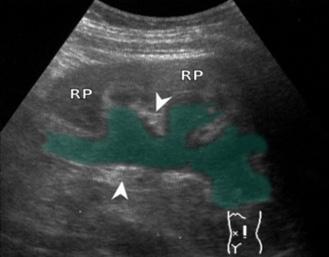

♦ Microangiopatía trombótica

♦ Estenosis de la arteria renal

♦ Nefritis tubulointersticial crónica

♦ Infecciones del tracto urinario / pielonefritis